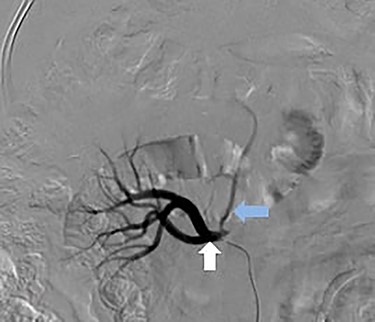

A 66-year-old male was referred to our institution for management of a liver lesion found incidentally on abdominal imaging. There was no significant past medical or surgical history, and he was asymptomatic. On physical examination, the patient was vitally stable and all systemic examinations were unremarkable. Contrast-enhanced triple phase abdominal computed tomography (CT) scan showed an arterial enhancing lesion in Segment I of liver with early washout, consistent with HCC (Fig. 1). This lesion received blood supply from the right renal artery (Fig. 2). Ultrasound-guided biopsy was performed to confirm the diagnosis of HCC, and subsequently the patient successfully underwent TACE. Figures 3 and 4 show the angiographic findings of the right renal artery branch supplying the lesion. Repeat CT scan at 6-week follow-up showed no evidence of residual disease.

Superselective delayed phase angiogram of right renal artery using microcatheter showing well-defined tumor blush.